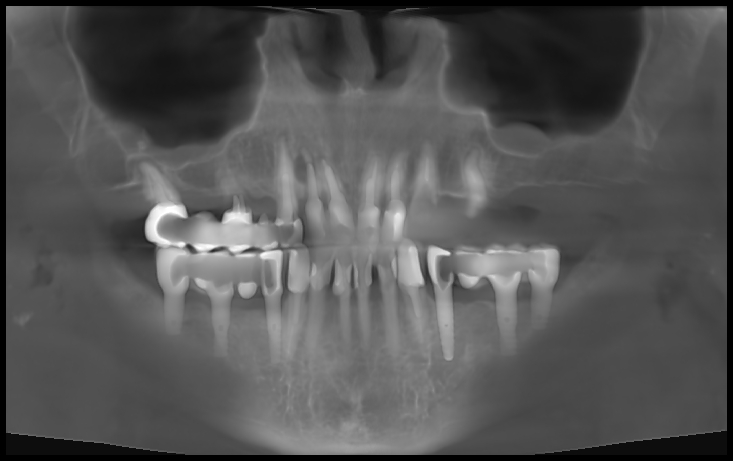

Кейс №5 - Установка 6 имплантов и несъемного протеза за 4 дня

02 Сентября 2020 Установка протеза по методике All-on-6

Проблема

Пациентка обратилась с жалобами на «нехватку» зубов на верхней челюсти, наличие воспалительных процессов и свищей в области старых металлокерамических протезов зубов на верхней челюсти. Пациентка была категорически против любых вариантов лечения, включающих в себя наращивание костной ткани, изучив большое количество информации в интернете.

Решение

На очной консультации после обследования полости рта и изучения данных 3D-исследования челюстей совместно с пациенткой был выработан план реабилитации верхней челюсти с использованием современной и эффективной методики протезирования All-on-6 (все на 6-ти).

Была проведена операция на верхней челюсти, во время которой:

• удалены несостоятельные металлокерамические протезы зубов,

• удалены разрушенные корни и все имеющиеся очаги воспаления,

• установлены 6 имплантатов,

• в последующие 4 дня изготовлен и зафиксирован несъемный эстетичный и функциональный протез.

Был достигнут отличный результат, что подтверждается красивой улыбкой благодарной пациентки.